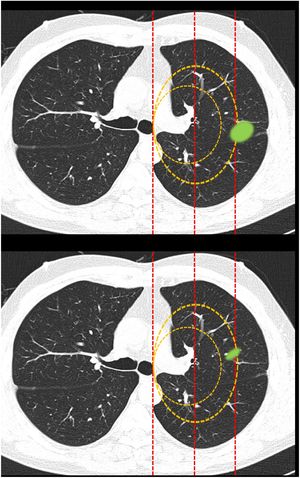

Clasificación de lesiones que sobrepasan líneas divisorias (fig. 2): en este bloque se valoró la uniformidad de criterio para clasificar una lesión como central (según una definición de centralidad (en los 2/3 internos) previamente establecida en el enunciado de la pregunta) en lesiones que sobrepasan las líneas divisorias, previamente trazadas en la imagen.

Figura 2.En este bloque se valoró la uniformidad de criterio para clasificar una lesión como central en lesiones que sobrepasan las líneas divisorias. Imagen 10: Considerando que la localización en los 2/3 internos del hemitórax corresponde con centralidad ¿Diría que el nódulo tiene localización? Central/Periférica. Imagen 11: Considerando que la localización en los 2/3 internos del hemitórax corresponde con centralidad ¿Diría que el nódulo tiene localización? Central/Periférica.

La mayoría de los participantes en la encuesta consideraron las lesiones según la mayor parte de su volumen se encontrase a un lado u otro de una línea divisoria previamente trazada en la imagen. Así pues, las lesiones predominantemente situadas en el lado periférico se catalogaron como periféricas (imagen 10) (92,8%) y las predominantemente situadas en el lado central, como centrales (imagen 11) (79,2%) sin apreciarse diferencias entre especialidades (tabla 2).

Categorización de lesiones que atraviesan líneas divisorias (con la mayor parte en la zona periférica Vs con la mayor parte en la zona central). La mayoría de los encuestados consideran que las lesiones se deben considerar según la mayor parte de su volumen se encuentre en un lugar u otro determinado. No se observan diferencias significativas entre grupos de especialidades diferentes ni para la primera pregunta ni para la segunda (aTest exacto de Fisher)